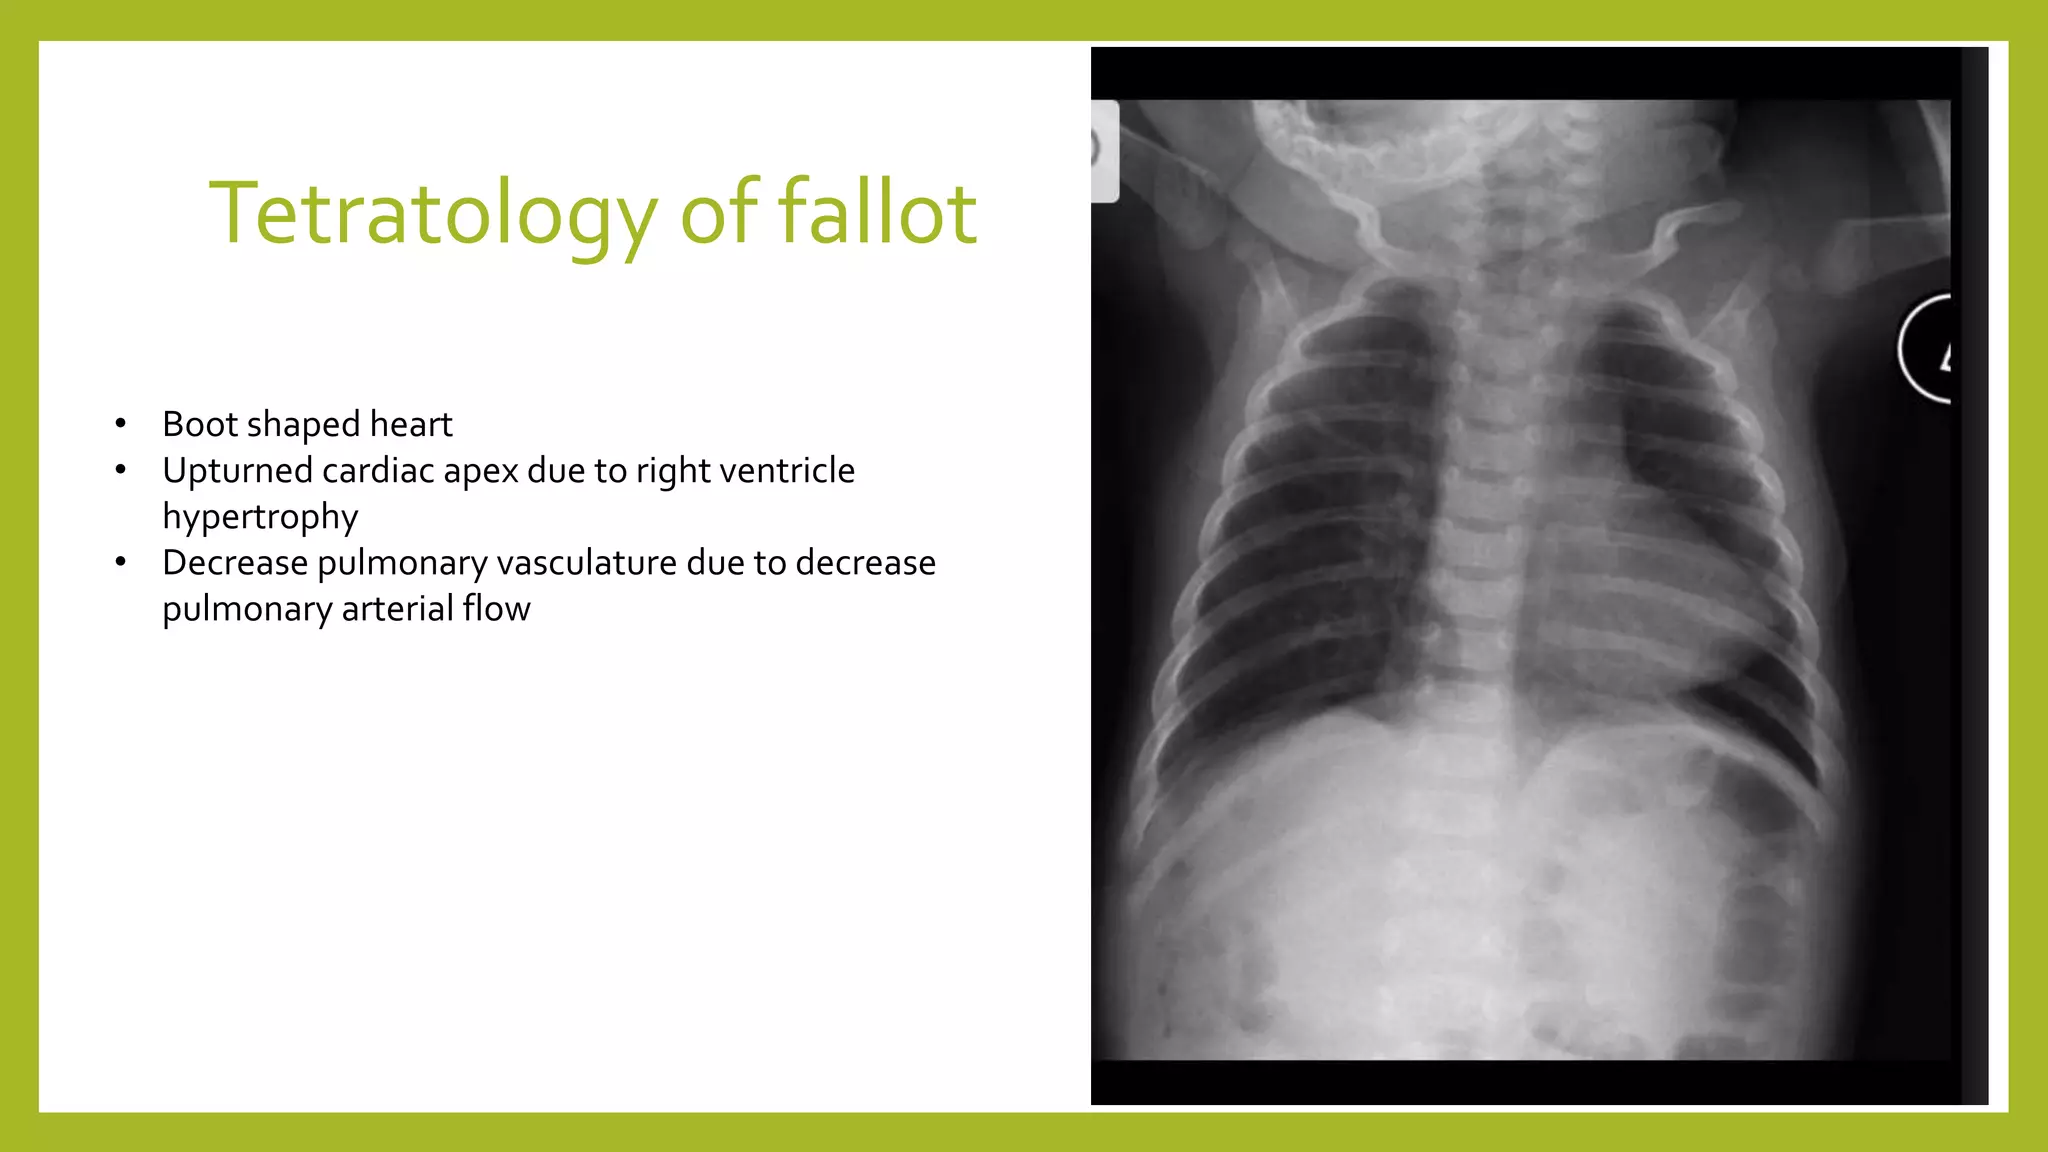

The document provides guidance on approaching and interpreting chest x-rays (CXR). It outlines steps to check the name, date and quality of the film, systematically scan the CXR looking for abnormalities, and determine if the lungs appear too white or black. Specific signs are described to help localize abnormalities, including the cardiac silhouette sign and pleural effusion signs. Examples are given of respiratory distress syndrome, tetralogy of fallot, transposition of great arteries, and total anomalous pulmonary venous return. The take home message is to summarize positive findings, compare to prior CXRs if available, and confirm findings with a radiologist.